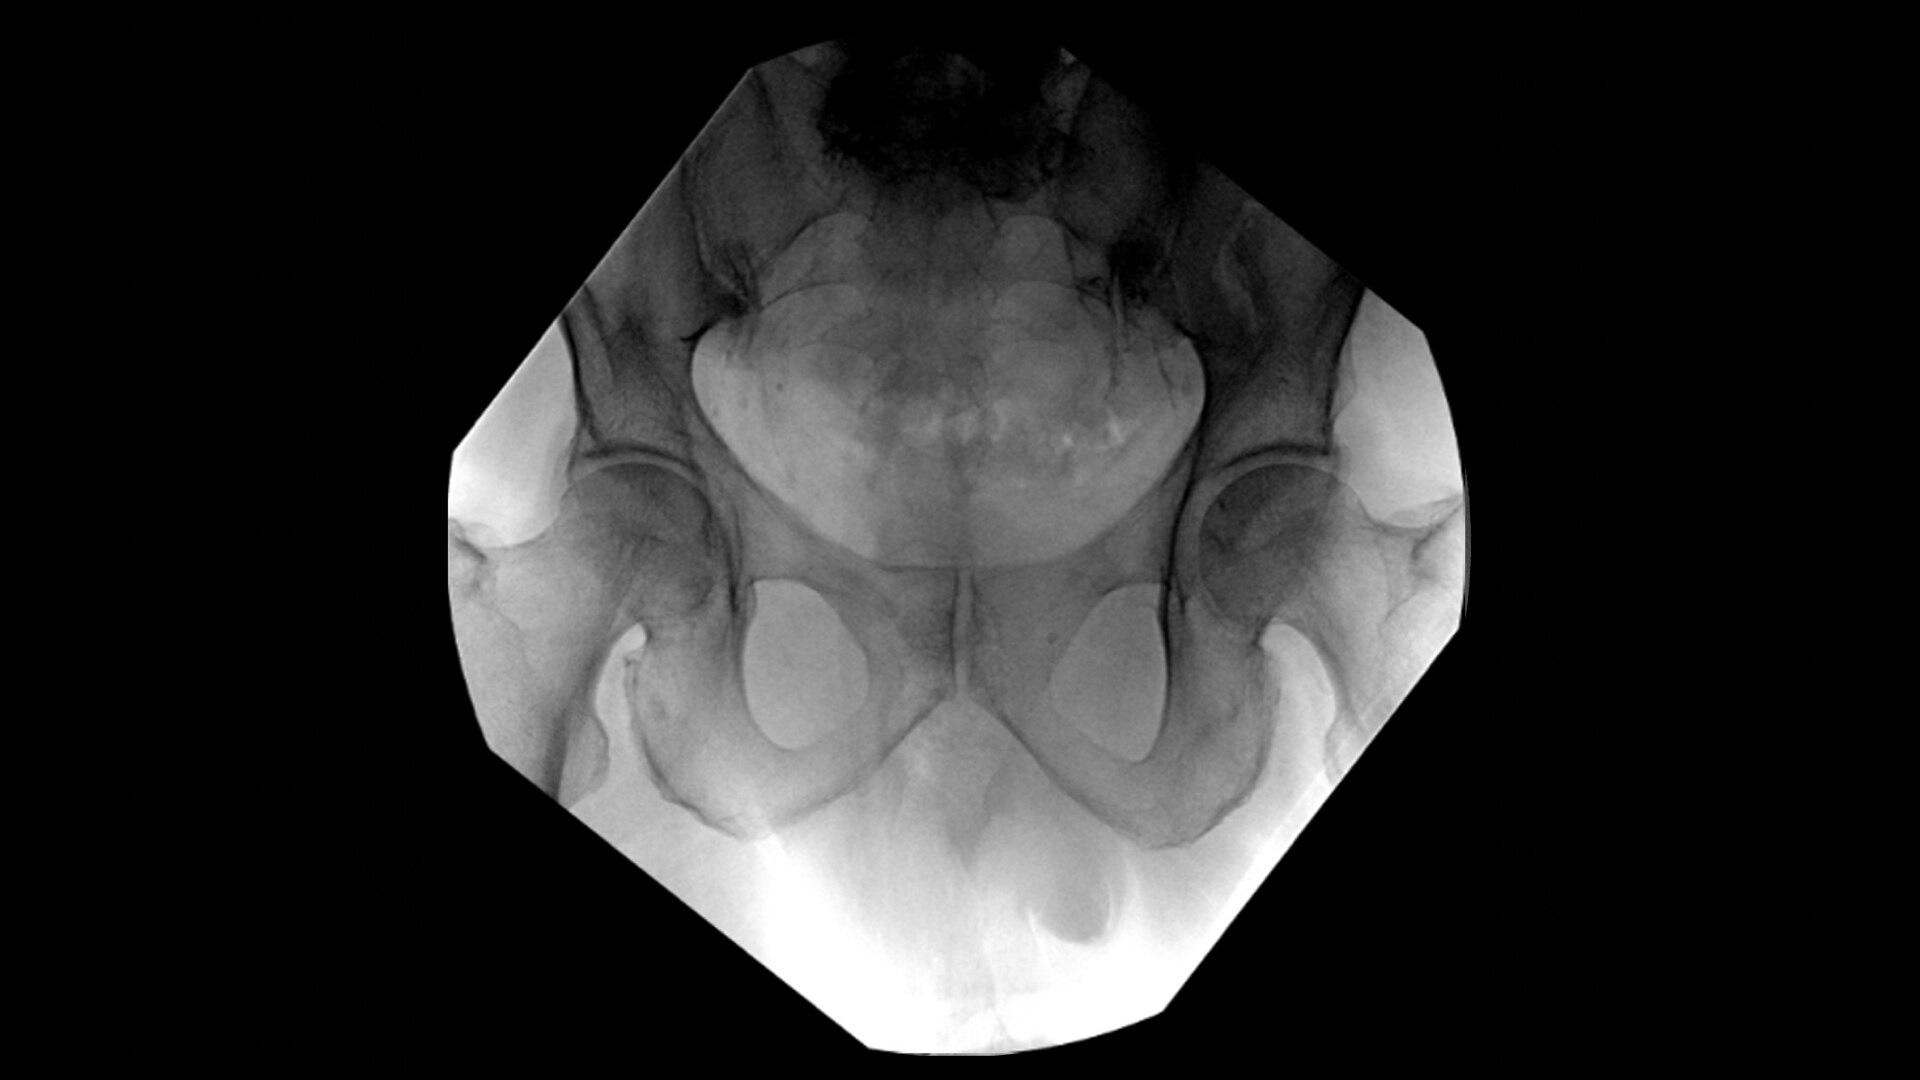

• Hip fracture fixation

• Hip replacement

During hip or femur imaging, capture up to 22% more Field of View by positioning detector closer to patient anatomy with the OEC low-profile X-ray tube housing compared to mono-block C-arms.

Complex orthopedic procedures require powerful imaging systems. OEC premium C-arms perform in a variety of procedures such as:

OEC C-arms provide orthopedic imaging with a large field of view optimized to clearly visualize orthopedic anatomy, such as the entire long bone femur or minute fractures in extremities. A clear display with comfortable viewing can easily show AP and lateral views, enabling efficient procedure planning.